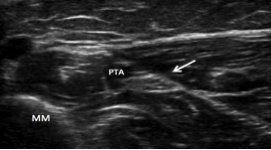

PTN blocks can be performed using landmark-based or ultrasound-guided techniques. The use of ultrasound has been shown to improve the success of sensory block.5